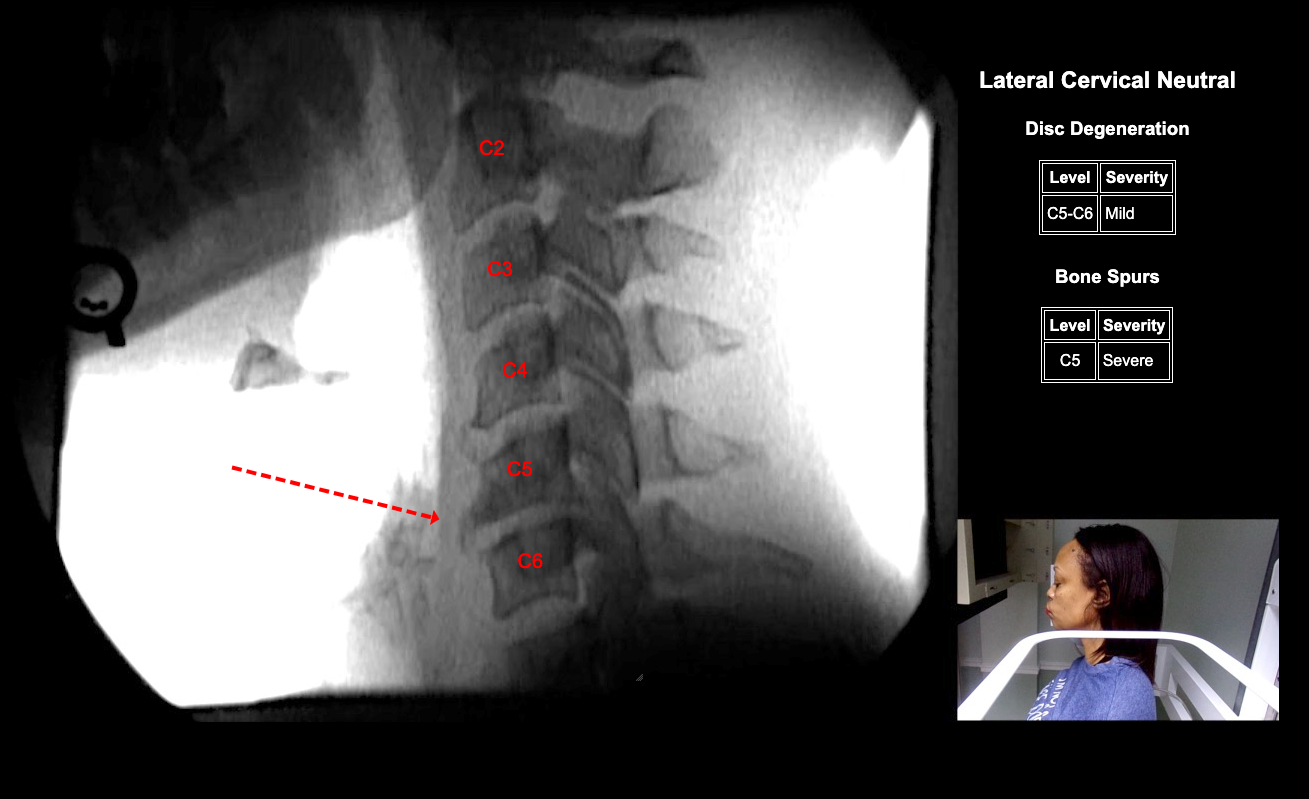

Image Name Image Type Image

Image 2